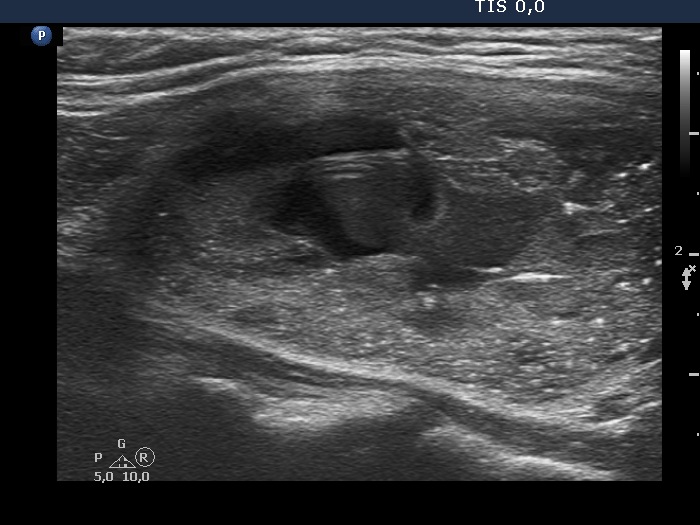

Ultrasonography. The thyroid was echonormal. There was a nodule presenting coarse calcification along its ventral surface. There was a spongiform-type cyst in the left lobe. The nodule has numerous echogenic figures most of them were caused clearly by posterior back wall enhancement.

Eight mL bloody cystic fluid was aspirated. After I aspirated 4 mL fluid, I have noticed that the cyst began to refill at once and a few minutes later the cyst became as large as before the aspiration.